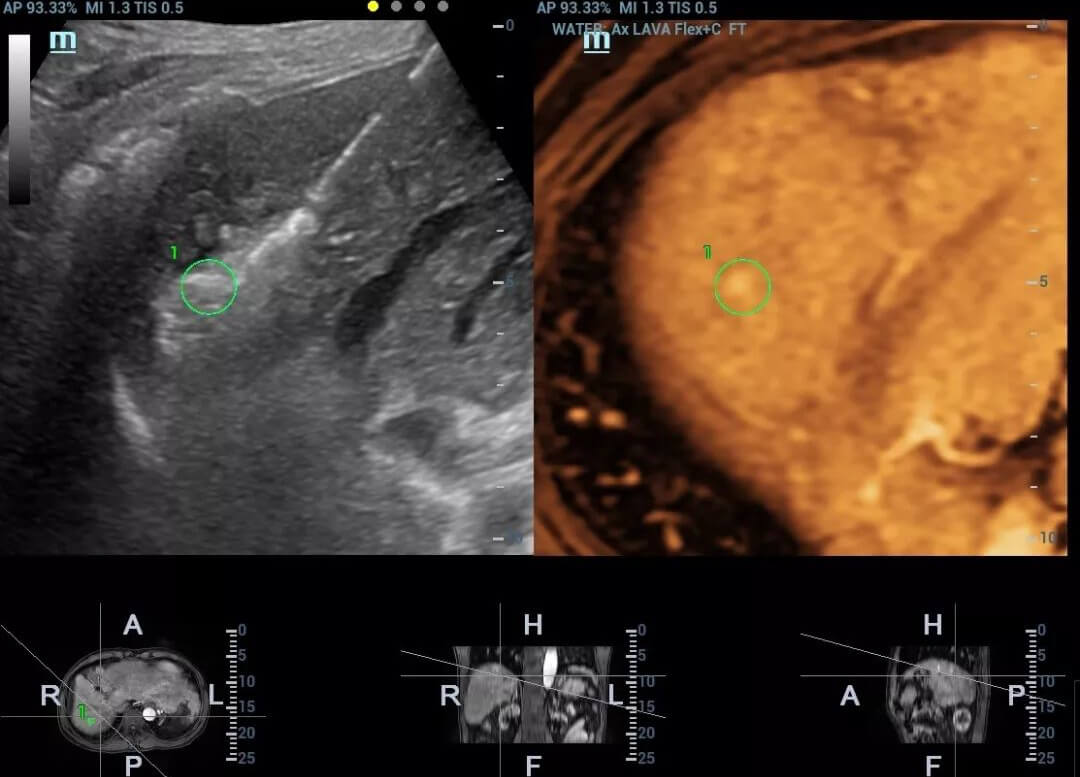

Apart from diagnosis, fusion imaging can also be applied in the ultrasound guided intervention procedure.

A typical clinical application scenario comes to the ultrasound-guided radiofrequency ablation when pure ultrasound fails to guide insertion of the needle accurately. In such case, based on lesion's target marker in both MRI and ultrasound images, Fusion can guide the needle tip to the lesion location precisely, increasing the accuracy of positioning effectively.

pc68-s5

Fusion in intervention procedure